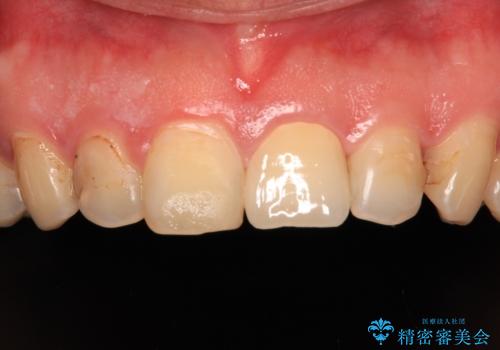

つぎはぎだらけの前歯をオールセラミッククラウンで自然な前歯に

むし歯で神経が取り除かれており、歯の変色と充填材の変色などにより、つぎはぎのような前歯となっていました。

膿の出口も認められたため、まずは根管治療を実施し、オールセラミッククラウンにて補綴治療を行うこととしました。

汚れがつきやすい状態のため、今後も継続してクリーニングを行っていく必要があります。